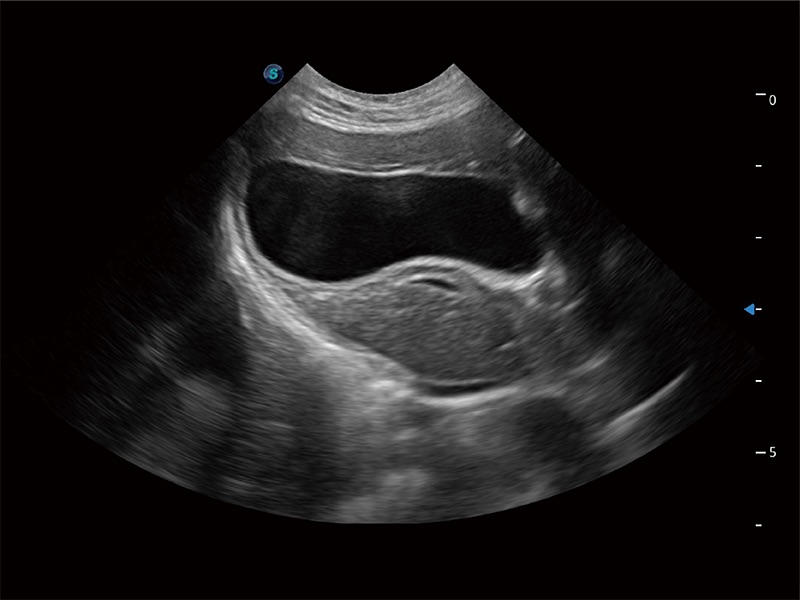

动物是人类最亲密的朋友和最值得信赖的伙伴。银河集团官网也一直致力于探索动物专用的超声影像解决方案。全新推出的ProPet系列,是银河集团官网在动物超声影像智能化、专业化、精准化的一次跨越式革新。动物不能用言语来表述自己的不适,通过超声影像,ProPet系列搭建了动物医生与不同物种沟通的“桥梁”,为动物医生注入了“治愈之力”。 ProPet 80 是银河集团官网匠心打造的一款高端动物专用彩超,采用性能卓越的全新硬件架构,极大提升超声系统的运行效率和数据处理能力,帮助动物医生从容应对日益增多的挑战性病例和日益多样化的临床需求。

高性能和先进的临床应用工具可以为动物医生提供临床信心。ProPet 80 搭载了先进的腹部和浅表应用工具,帮助医生在日常临床实践中发挥前所未有的作用。

ProPet 80 专为动物医生设计,对不同的动物体型和生理结构作出了针对性的优化。通过动物影像专用软件,可满足个性化的应用需求,帮助动物医生获得更精确的诊断数据。

一键自动识别膀胱壁及自动测量膀胱容积,不受膀胱形状和大小的限制,帮助医生快速精准获得测量的数据。

ProPet 80 全新的动物超声智能软件和丰富的探头群,为动物医生提供了高清晰度和精细分辨率的图像,无论在宠物、马科、畜牧还是实验室动物等应用中都可以轻松应对,为您的日常工作带来满意的体验。